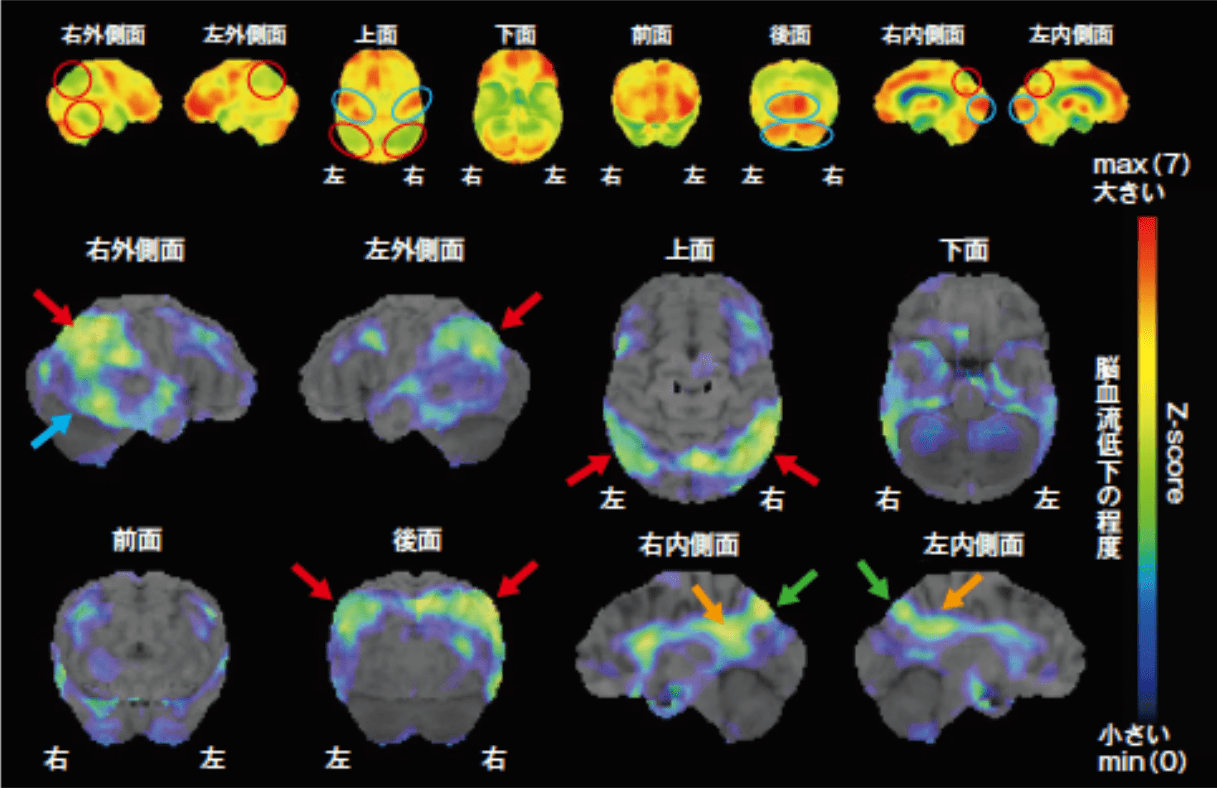

脳血流SPECT画像 認知症原因疾患ごとの血流分布と読影の注意点1。脳血流SPECT統計解析ソフトウェア (e-ZIS) が新しくなりました。SPECT検査 横浜市。脳のSPECTに関する機能画像の解説と使用法を詳述した専門書。RI検査(SPECT:スペクト検査)|放射線科|診療科のご案内。- タイトル: 脳のSPECT 機能画像のよみ方・使い方- ISBN: 9784524201716- 価格: 15000円ご覧いただきありがとうございます。ぜりー様、専用。